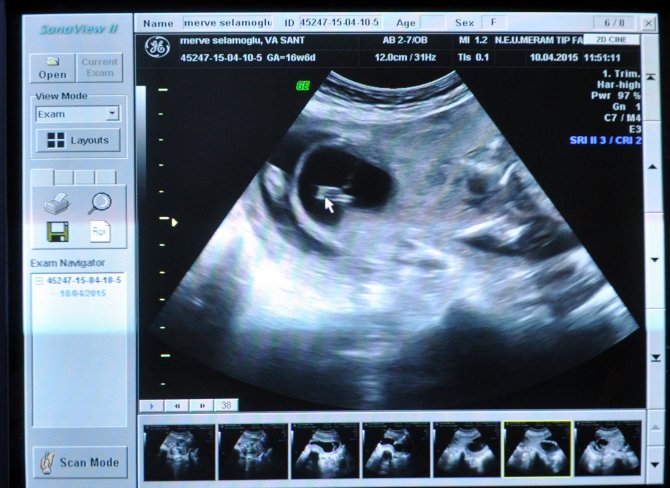

KONYA (AA) - METİN BOLAT - Konya'da Merve öğretmen, karnındaki bebeğin böbreklerinde sorun bulunması nedeniyle yapılan "Gebeliği sonlandıralım, zaten ölecek" önerisini kabul etmedi. Bebek 17 haftalık ve 250 gramken, nadir yapılan bir ameliyatla yaşatıldı.

Acar ve ekibinin gerçekleştirdiği operasyonla, 17 haftalık ve 250 gram ağırlığındaki bebek, idrar torbası ile sıvı etrafındaki bölgeye yerleştirilen şantla böbrekleri rahatlatılarak yaşatıldı.

"Anne, gebeliğin devam etmesini istiyordu. Biz de 17 haftalık olan 250 gramlık bebeğin, böbreğine yerleştirdiğimiz şantla yaşamasını sağladık. Şantın bir ucu çocuğun idrar torbasında kalacak şekilde, diğer ucu da karnın dışında, rahmin etrafındaki boşluğa yerleştirdik. Bu sayede böbrekte idrar birikmeden anne karnındaki sıvıyı oluşturmuş olduk. Çocuğun yaşamasını sağlayan bu sıvı oldukça önemli. Gebelik şu an iyi gidiyor. İşlemi yapmamış olsaydık 4,5 aylık bebeği kaybedecektik."